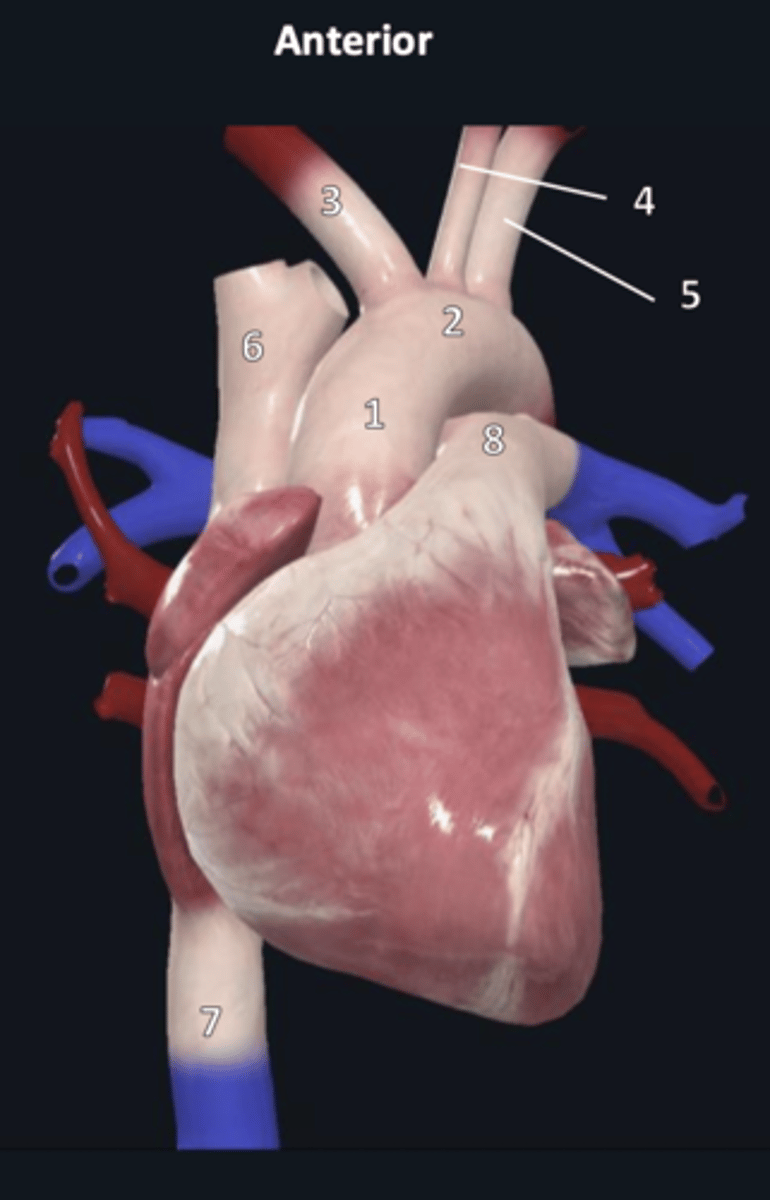

right coronary artery

1

anterior interventricular artery

2 (red)

great cardiac vein

3 (blue)

anterior interventricular artery

2 (red)

great cardiac vein

3 (blue)

left marginal artery

4

left marginal vein

5

posterior left ventricular artery

6

posterior vein of left ventricle

7

coronary sinus

8

right coronary artery

1 (red)

great cardiac vein

3

posterior left ventricular artery

6

posterior vein of left ventricle

7

coronary sinus

8

right posterolateral artery

9

middle cardiac vein

10

posterior interventricular artery

11

right marginal artery

12

small cardiac vein

13